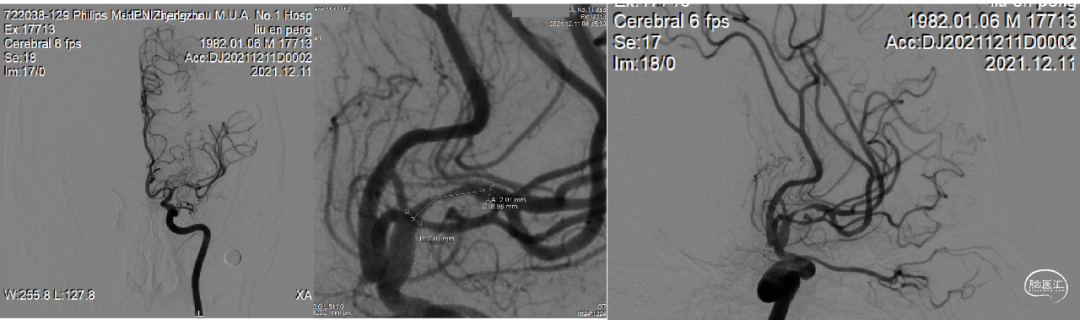

DSA提示:右侧大脑中动脉M1起始部极重度狭窄、次全闭塞,狭窄远端M1段管径约2.1mm,近端颈内动脉末端管径约3.3mm;M2段主干中度狭窄,分水岭下移;颈内动脉入路非常迂曲。

予缓慢充盈球囊至10atm,透视下观察球囊已充盈饱满,静待20秒,缓慢泄压球囊,造影提示局部管腔毛糙并粗细不均,担心弹性回缩基础上伴夹层形成。

撤出球囊,交换XT-27微导管小心通过狭窄,稳定释放Neuroform EZ 3.5mm×20mm支架。

借助支架输送系统回送支架导管至支架尾端顶住再撤出支架系统,保留微导丝,观察20分钟,见血流通畅,撤出微导丝,回撤导引导管和中间导管,正侧位减影和非减影像造影提示大脑中动脉血流通畅良好,支架远近端均匀贴壁,分水岭恢复正常。